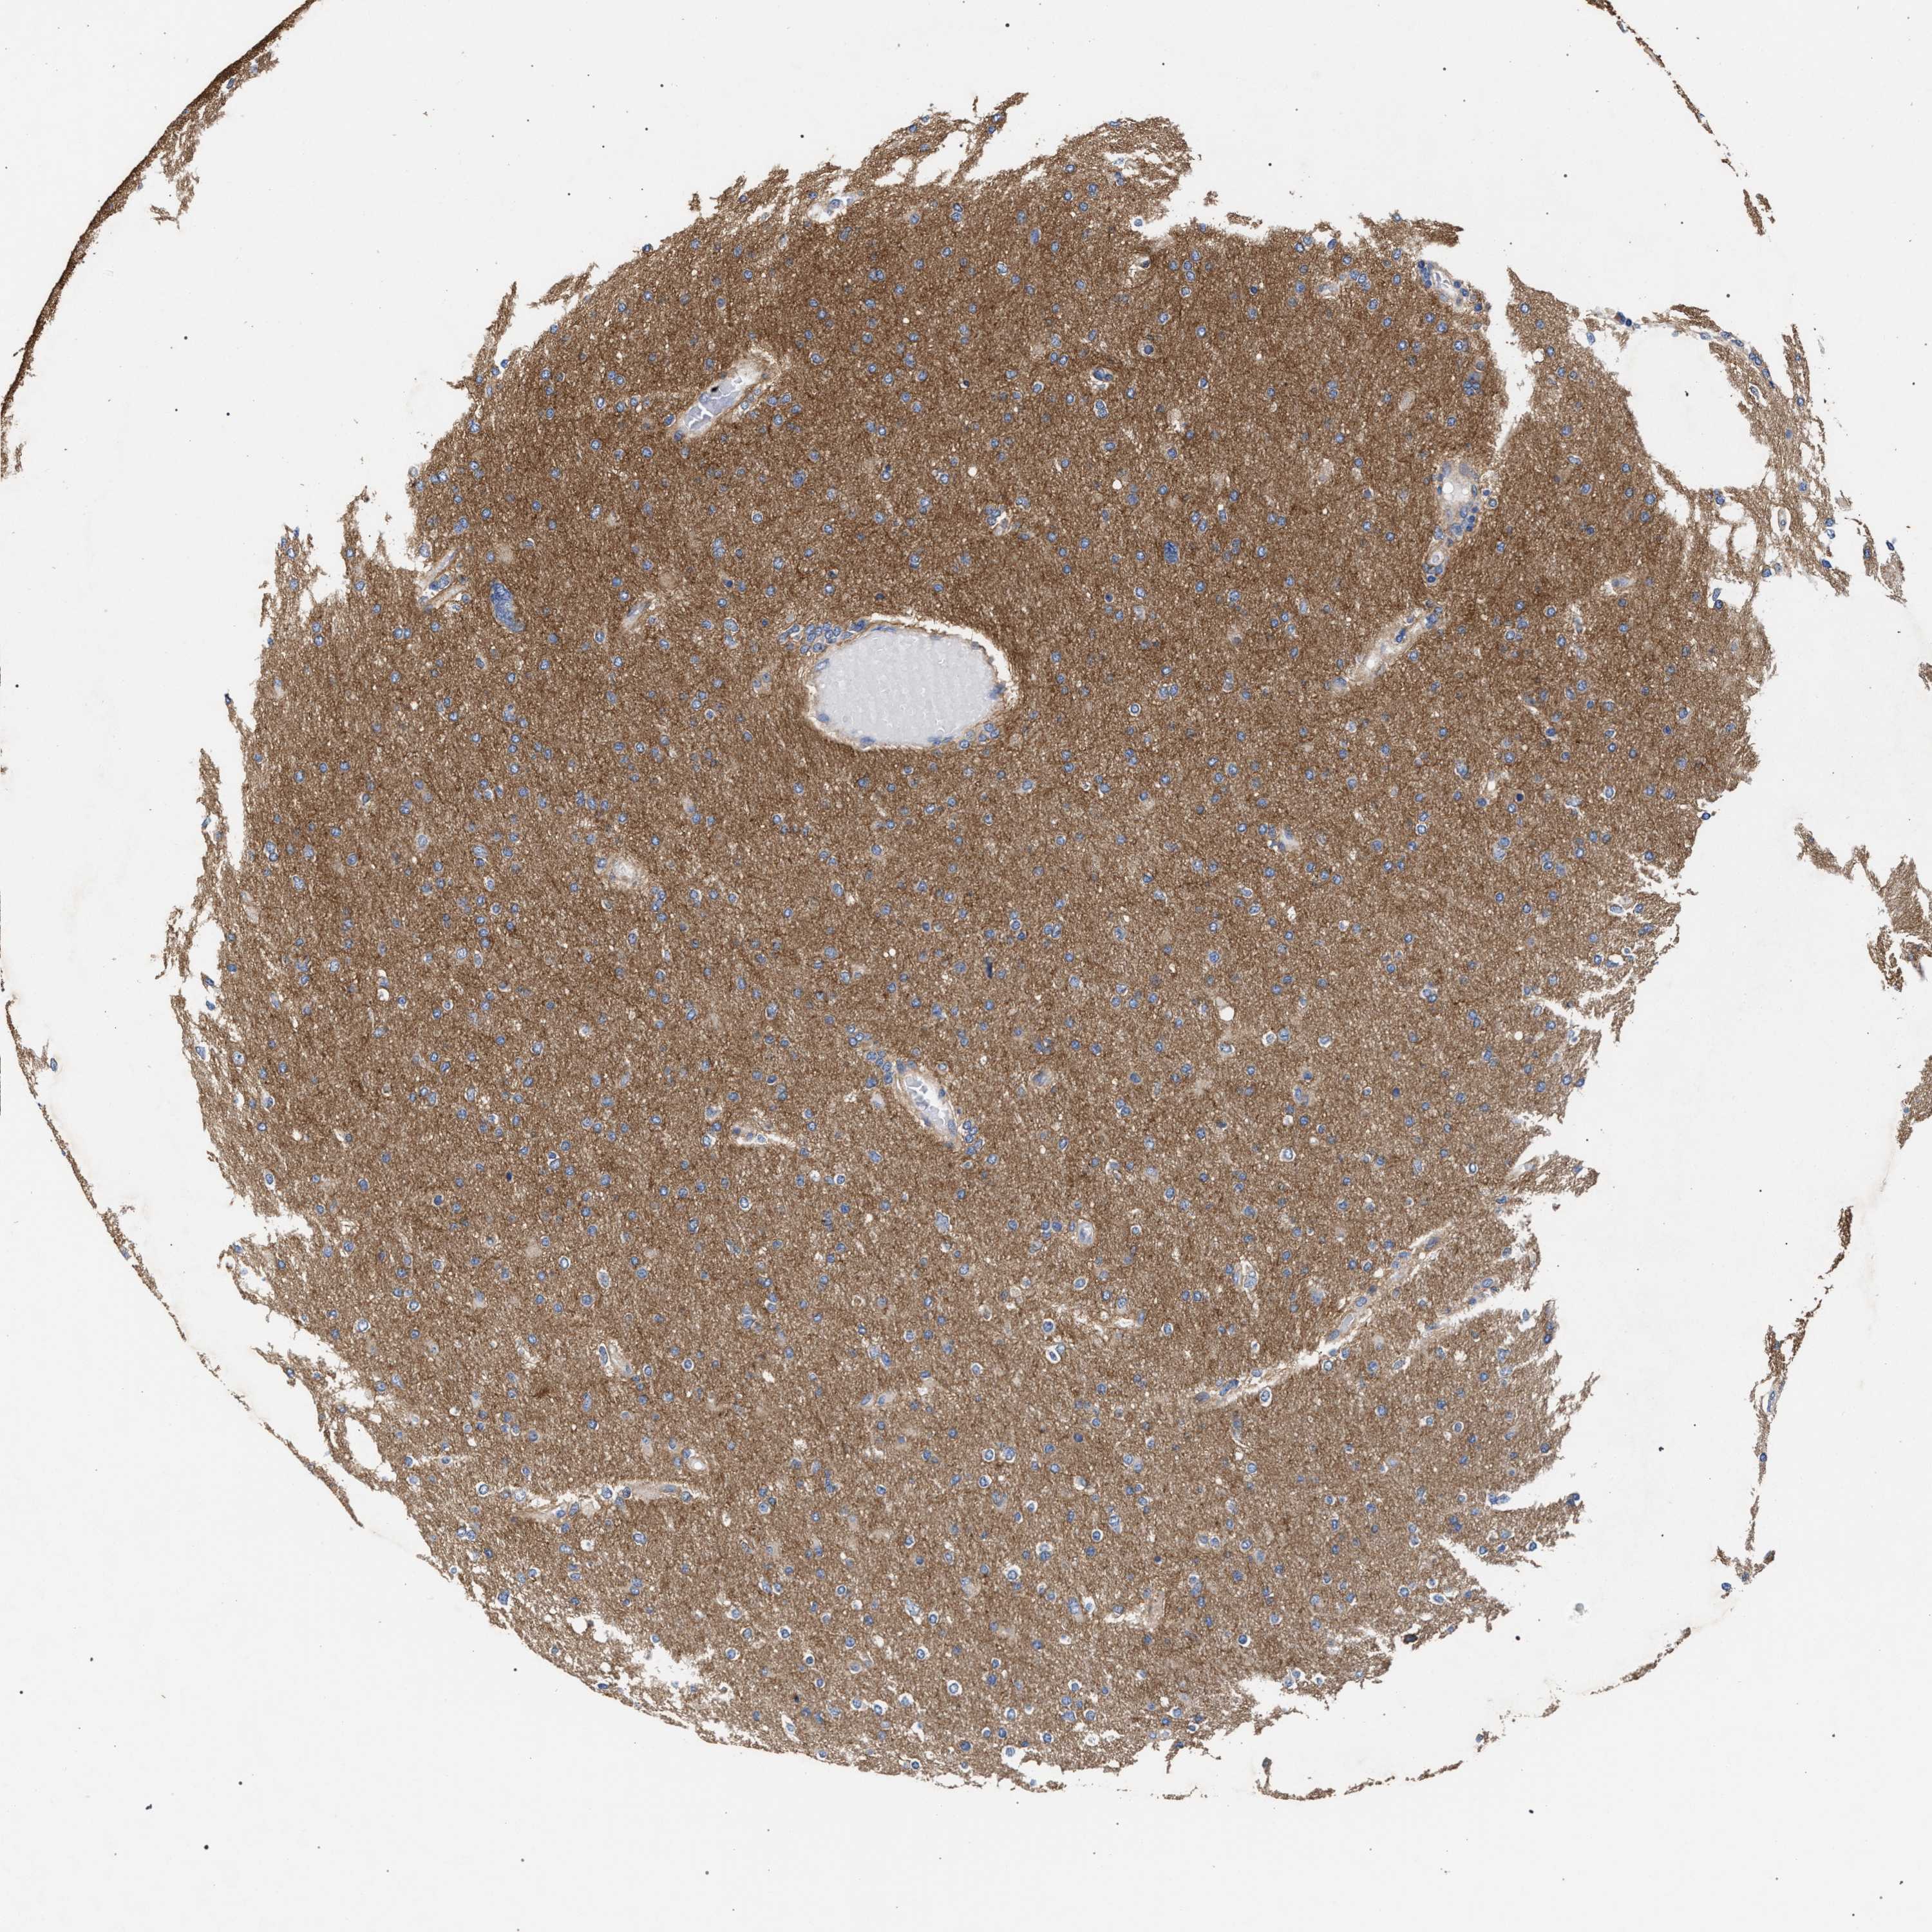

GLIOMA - Protein expressioni

A mouse-over function shows sample information and annotation data. Click on an image to view it in a full screen mode. Samples can be filtered based on level of antibody staining by selecting one or several of the following categories: high, medium, low and not detected. The assay and annotation is described here.

Antibody stainingi

Antibody staining in the annotated cell types in the current human tissue is reported as not detected, low, medium, or high, based on conventional immunohistochemistry profiling in selected tissues. This score is based on the combination of the staining intensity and fraction of stained cells.

Each image is clickable and will lead to virtual microscopy that enables deeper exploration of all samples and also displays staining intensity scores, fraction scores and subcellular localization as well as patient and tissue information for each sample.

Antibody HPA021261

Antibody HPA021325

Staining

High

Medium

Low

Not detected

Intensity

Strong

Moderate

Weak

Negative

Quantity

>75%

75%-25%

<25%

None

Location

Nuclear

Cytoplasmic/membranous

Cytoplasmic/membranous,nuclear

Glioma, malignant, High grade

Glioma, malignant, Low grade